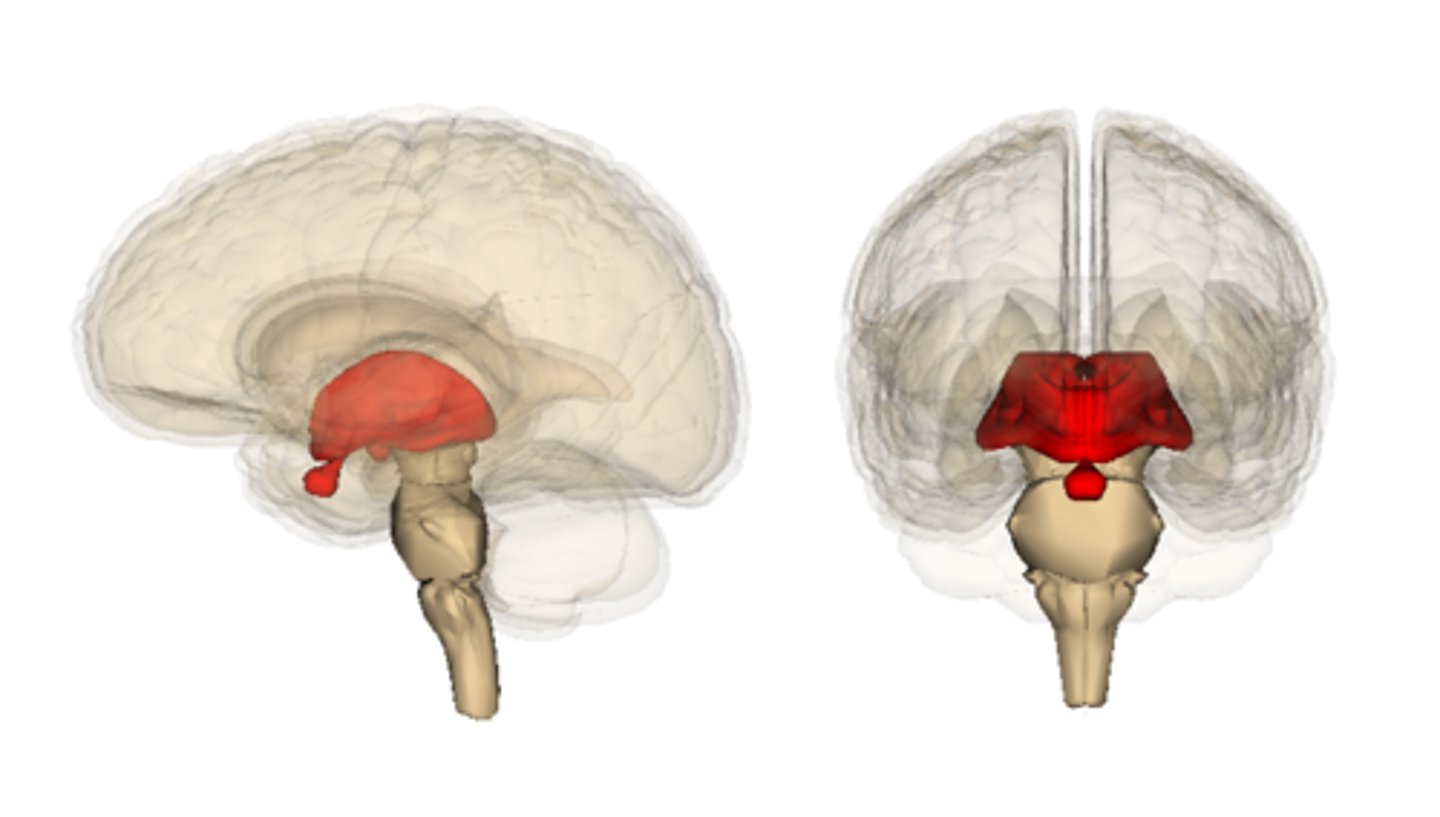

diencephalon

thalamus, hypothalamus, epithalamus

thalamus location

pair of oval masses of gray matter

thalamus function

relay station for sensory impulses, pain

Hypothalamus location

hypothalamus function

autonomic control (heart rate, blood pressure, digestion)

emotions/behavioral drives (aggression, fear, content, sex drive, thirst center)

endocrine (hormones)

body temperature

Epithalamus location

contains the pineal gland

epithalamus function

secretes melatonin